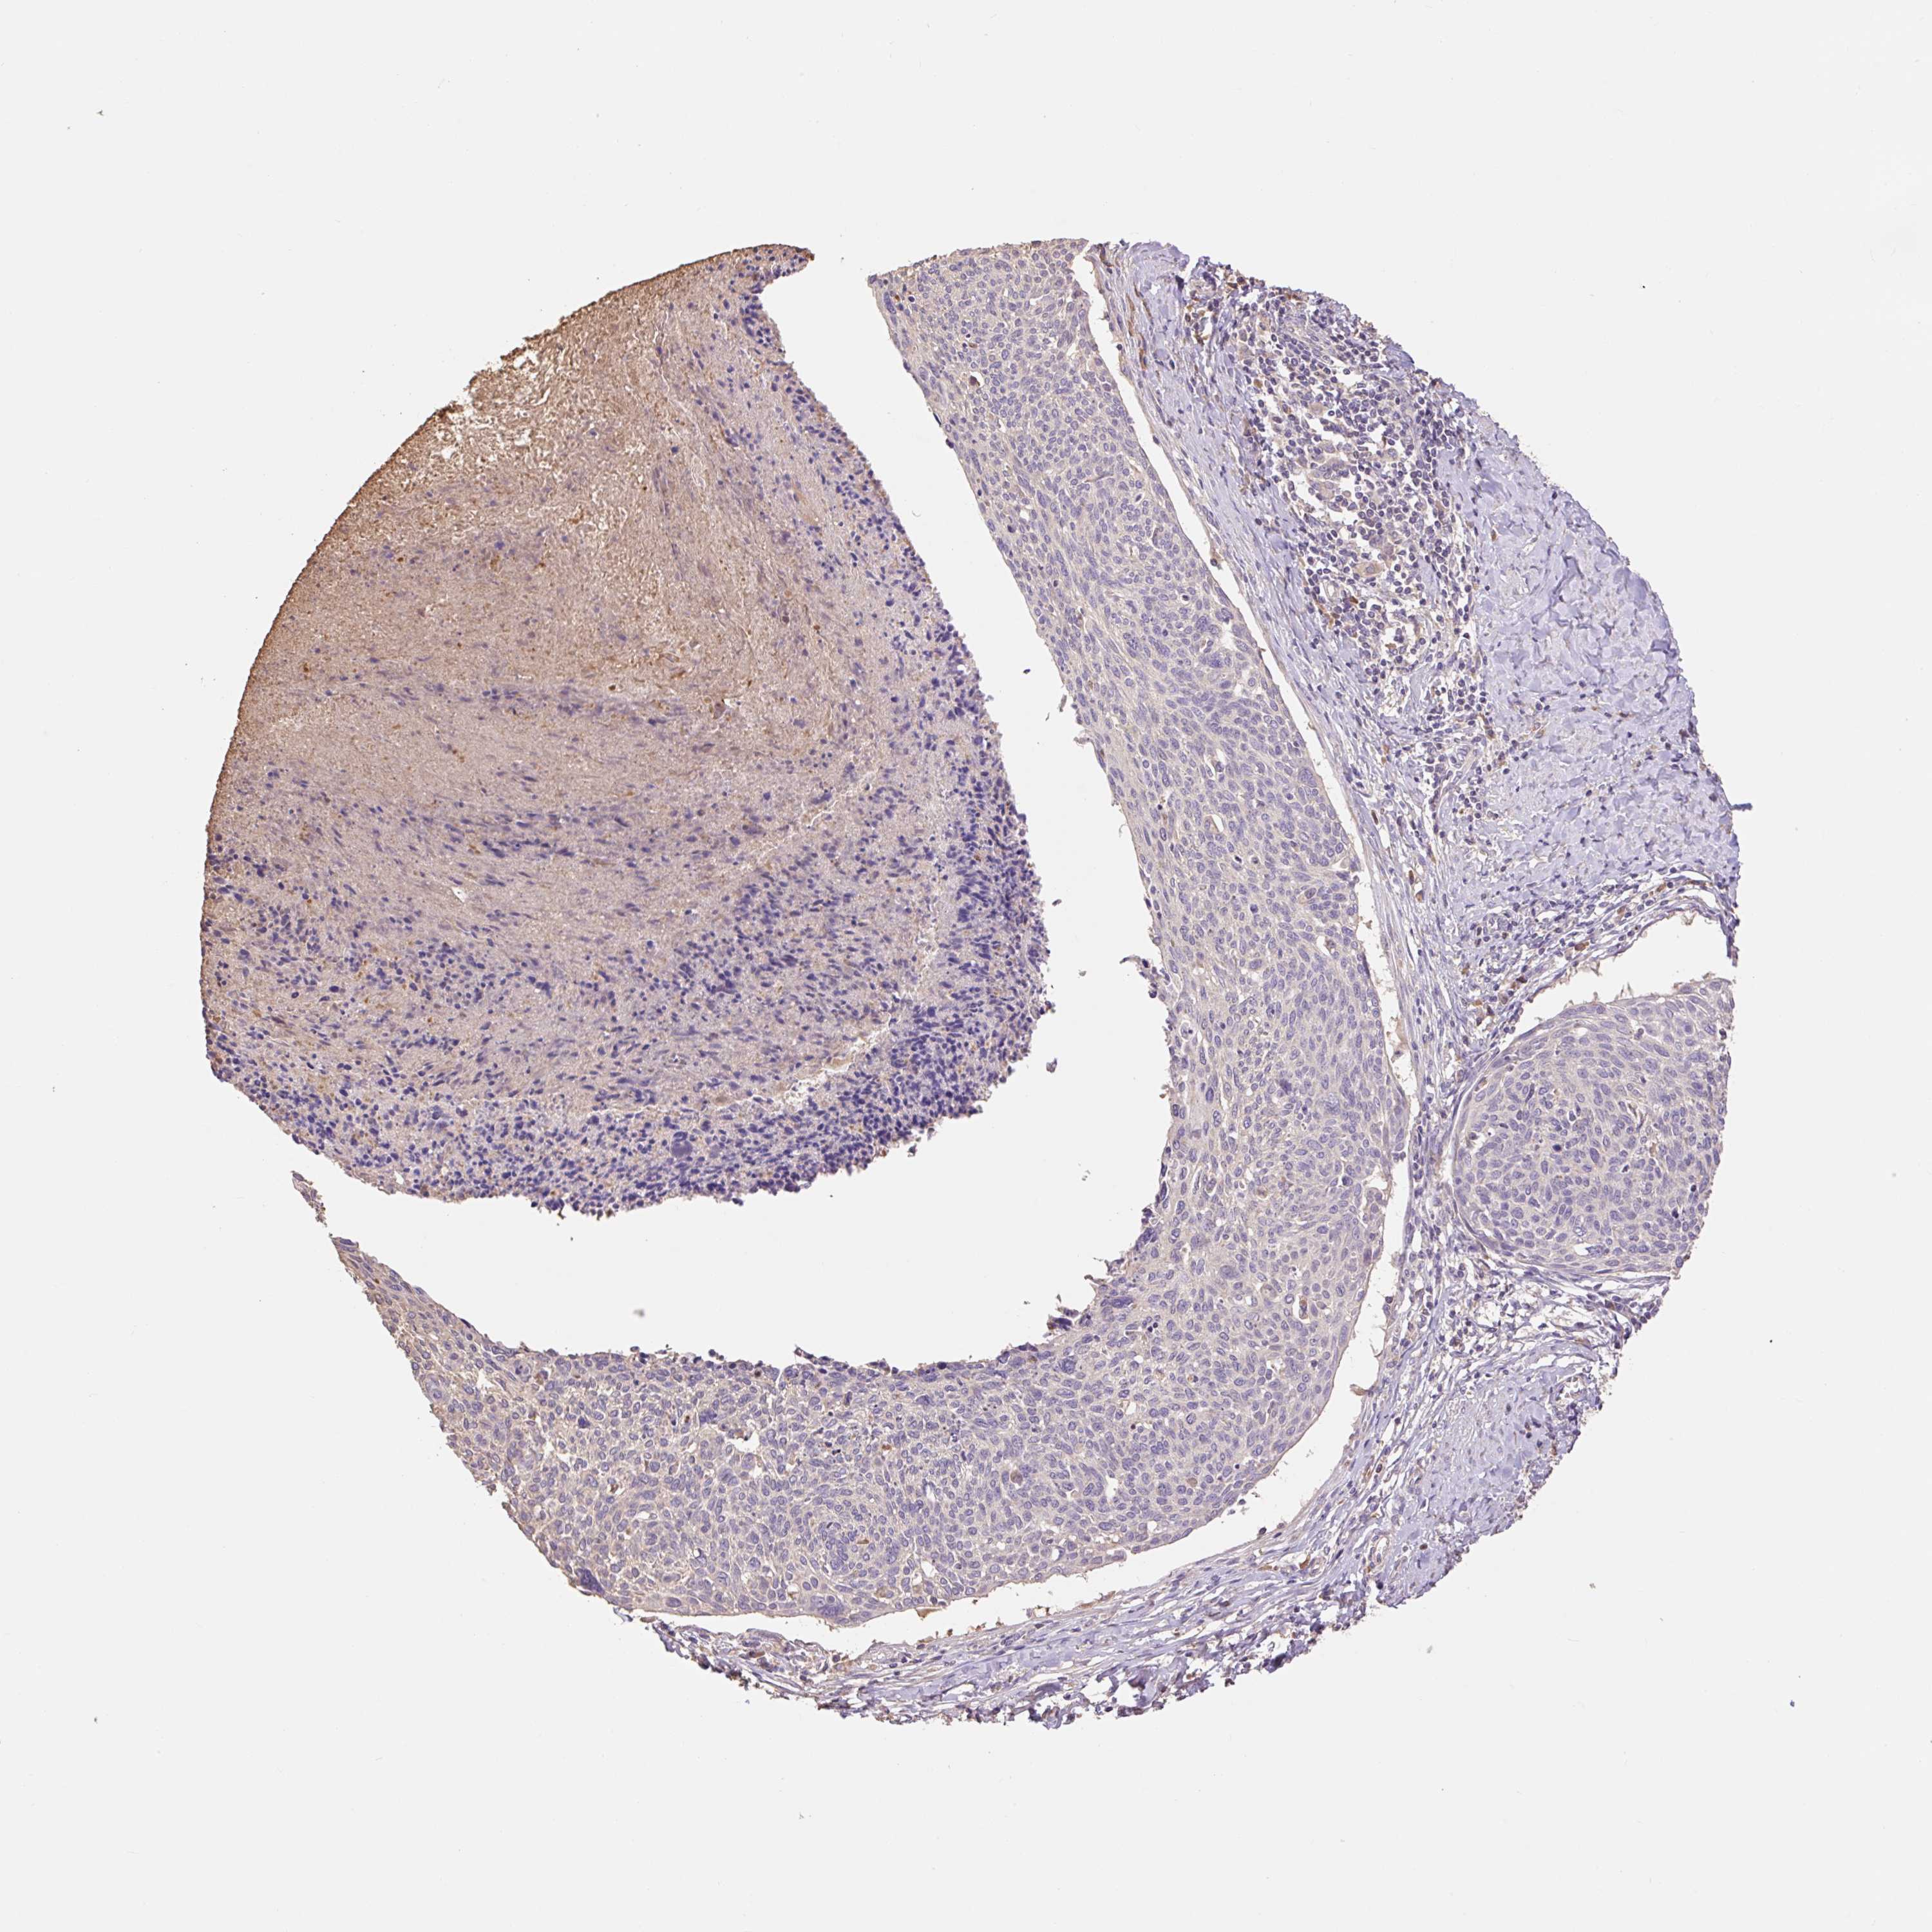

CERVICAL CANCER - Protein expressioni

A mouse-over function shows sample information and annotation data. Click on an image to view it in a full screen mode. Samples can be filtered based on level of antibody staining by selecting one or several of the following categories: high, medium, low and not detected. The assay and annotation is described here.

Note that samples used for immunohistochemistry by the Human Protein Atlas do not correspond to samples in the TCGA dataset.

Antibody stainingi

Antibody staining in the annotated cell types in the current human tissue is reported as not detected, low, medium, or high, based on conventional immunohistochemistry profiling in selected tissues. This score is based on the combination of the staining intensity and fraction of stained cells.

Each image is clickable and will lead to virtual microscopy that enables deeper exploration of all samples and also displays staining intensity scores, fraction scores and subcellular localization as well as patient and tissue information for each sample.

Antibody HPA053415

Staining

High

Medium

Low

Not detected

Intensity

Strong

Moderate

Weak

Negative

Quantity

>75%

75%-25%

<25%

None

Location

Nuclear

Cytoplasmic/membranous

Cytoplasmic/membranous,nuclear

Squamous cell carcinoma, NOS

Adenocarcinoma, NOS